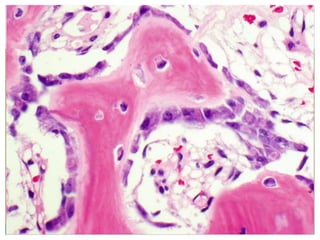

SKELETAL CARTILAGE • Chondrocytes: •Lacunae: . • Extracellular matrix: • Perichondrium:

Hundreds of EyesStaring Back at YOU!

Hundreds of Eyes Staring Back at YOU!